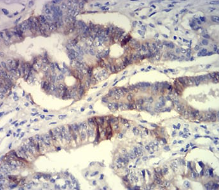

CD239 Mouse Monoclonal antibody[5C5A6]

Immunogen:    Purified recombinant fragment of human CD239 (AA: extra 32-197) expressed in E. Coli.

IHC    1/200 - 1/1000